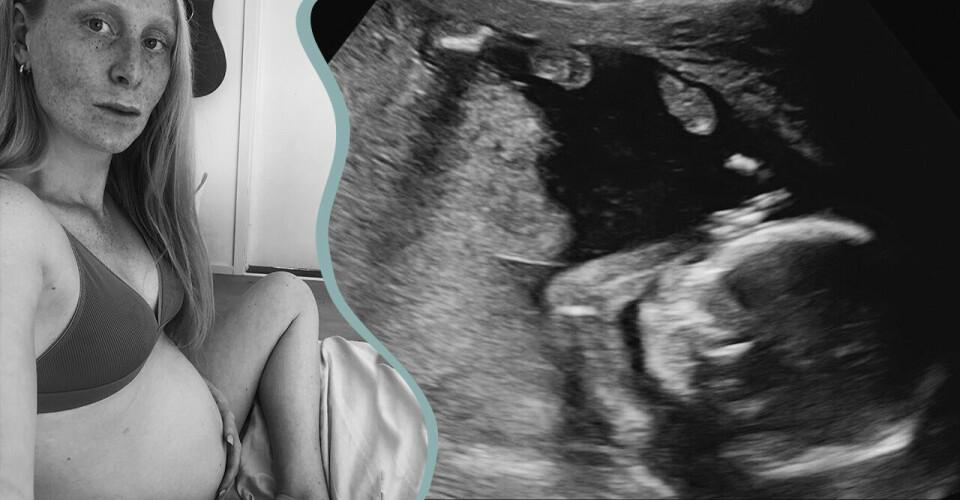

Stockholmaren Lisa Segerson, 29, är gravid med sitt första barn, och i fredags sa samtliga chefer upp sig från SÖS förlossningsavdelning och 40 procent av barnmorskorna på Danderyds sjukhus har slutat i protest. Här är hennes krönika om hur det är att vara höggravid under den brinnande förlossningskrisen i Stockholm 2021.

Fredag eftermiddag. Vecka 32. Sitter och stirrar på ”att köpa”-listan. Får hjärtklappning av minus på bankkontot. Hur får man barnet att ta bröstet? Behövs verkligen ett babygym? Kanske ska man gå en amningskurs?

Mobilen fylls av meddelanden. ”Så var det för mig också, men det gick jättebra ändå.” och ”Precis så där stod det inför min förlossning – läs inte för mycket, du ska inte oroa dig i onödan”. Messar min partner. Han råder mig att logga ut och slappna av. Men jag kan inte slappna av. Inte i dag. För jag bor i Sveriges rikaste region, ska snart klämma ut ett livslevande barn på gissningsvis 3,5 kg ur min vagina och vi är mitt i en förlossningskris som inte verkar ha ett slut. Och jag ska trösta mig med att det typ alltid varit så här?

Jag tvivlar dock inte på att jag och min partner kommer att få den bästa vården efter de förutsättningarna som finns och jag imponeras dagligen av alla magiska barnmorskor som förlöser våra barn. Men när jag ser rubrikerna om rådande situation så kan jag inte tänka annat än: börjar vi närma oss en bristningsgräns? När kommer den riktiga katastrofen, eller är vi mitt i den? Måste vi (då menar jag mig och mitt massiva tjejgäng med förstföderskor 2022) helt enkelt blunda för fakta för att kunna genomföra det som ligger framför oss? För att för oss finns det ingen annan utväg. Ingen nödutgång, sjukskrivning eller uppsägning. Vi möter den där förlossningen oavsett hur bemanningen ser ut.

Jag lämnar frågan där. För jag är för trött. Och mitt barn sparkar diagonalt och träffar otroligt nog revben och urinblåsa samtidigt. Ja, ni som vet - ni vet. Jag kan heller inte hjälpa att känna en viss hopplöshet. Eller är det hjälplöshet? Gravida kvinnor tränar på att släppa kontrollen, läser sig till olika tekniker för att motverka förlossningsrädsla, gör allt ”by the book”. Men när dagen D väl är kommen så återstår fortsatt frågorna: Finns det en ledig vårdplats för mig i dag? Har barnmorskorna tid att förlösa mitt barn? Frågor som legat där i flera år. För sådan bara är förlossningsvården i Stockholm. Som att jag ska köpa det.